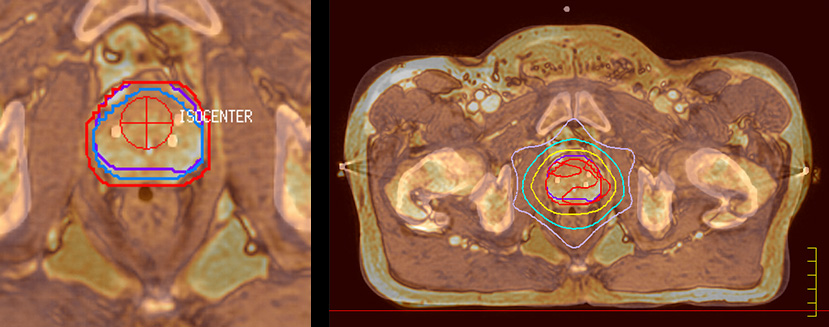

Impressive clinical benefits for prostate

“The biggest problem for CT-based planning, especially in prostate, is you can’t see the cancer very well,” says Dr. Stevens. “On CT it can be quite challenging to see the edge of the prostate especially at the apex. When the edge of the prostate can’t be delineated well on CT, radiation oncologists will increase their margins a little bit so they don’t miss it, but that can also increase toxicity.”

“Using MR, the prostate is well delineated. We quickly see the edges of cancerous tumors like in prostate cancer, and as normal structures can be defined, we can optimize the treatment plan to protect these organs and their normal function. This can potentially improve the outcome. And it improves workflow as well. We can contour more quickly, confident that the tumor is going to be in the field.”

“When a patient registers, first CT simulation and MR simulation are done, followed by CT-MR registration on Pinnacle3. Then the target and normal organ delineation is performed on MR images. Meanwhile we create a reference CT image for online treatment and localization correction. During the treatment phase we can perform additional MRI scans to visualize the anatomy changes and create an adaptive plan. This plan basically adapts the treatment plan to the changes.”